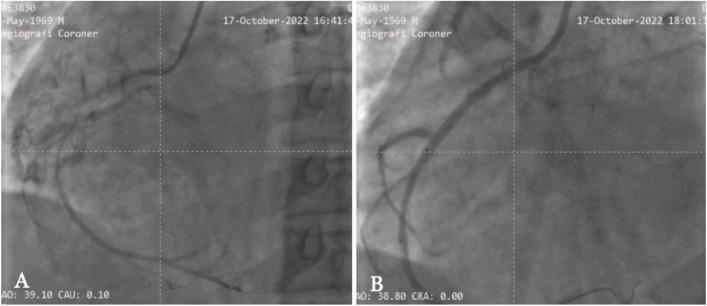

One of the most difficult procedures in interventional cardiology is the percutaneous coronary intervention (PCI) on a chronic total occlusion (CTO) lesion case. To rate the difficulty of guidewire crossing, several angiographic scoring methods have been developed such as the Japan CTO (J-CTO) score. Here we demonstrate the advantages of revascularization using PCI procedure in a CTO case with intractable heart failure. A 53-year-old man presented to the emergency room of Dr. Zainoel Abidin Hospital, Banda Aceh, Indonesia with acute decompensated heart failure. The patient had a history of past PCI with two patent drug eluting stents (DES): one in the left main (LM)-left anterior descending (LAD) artery and one in the distal left circumflex (LCX) artery. The patient had three times rehospitalizations in the last three months. According to single-photon emission computed tomography (SPECT) imaging, the right coronary artery was remained functional; however, the lesion was categorized into very difficult level (J-CTO >3). The PCI was carried out on the right coronary artery and the blood vessel was successfully revascularized after applying multiple techniques. Following the procedure, the heart failure was treated and the 6-minute walking test (6MWT) that performed 12 days after the PCI increased from 220 to 260 meters. The success of this case depended on a comprehensive history taking, adequate imaging methods, and the selection of the proper tools and PCI strategy. In conclusion, despite the challenges, PCI is still an option for patients with persistent complete occlusion. The PCI requires comprehensive preparation and the use of angiographic scoring systems, such as the J-CTO score, to determine the approach and the likelihood of success.

介入心脏病学中最具挑战性的操作之一是针对慢性完全闭塞(CTO)病变病例进行经皮冠状动脉介入治疗(PCI)。为了评估导丝通过的难度,已经开发了多种血管造影评分方法,如日本CTO(J-CTO)评分。在此,我们展示了在一例伴有顽固性心力衰竭的CTO病例中使用PCI进行血运重建的优势。一名53岁男性因急性失代偿性心力衰竭被送往印度尼西亚班达亚齐宰诺埃尔·阿比丁博士医院的急诊室。该患者既往有PCI病史,植入了两枚药物洗脱支架(DES):一枚位于左主干(LM)-左前降支(LAD)动脉,另一枚位于左旋支(LCX)动脉远端。该患者在过去三个月内三次住院。根据单光子发射计算机断层扫描(SPECT)成像,右冠状动脉仍有功能;然而,该病变被归类为极难级别(J-CTO>3)。在右冠状动脉上进行了PCI,应用多种技术后血管成功实现血运重建。术后,对心力衰竭进行了治疗,PCI术后12天进行的6分钟步行试验(6MWT)从220米增加到了260米。该病例的成功取决于全面的病史采集、充分的成像方法以及合适工具和PCI策略的选择。总之,尽管存在挑战,但PCI仍是持续性完全闭塞患者的一种选择。PCI需要全面的准备,并使用血管造影评分系统,如J-CTO评分,来确定治疗方法和成功的可能性。